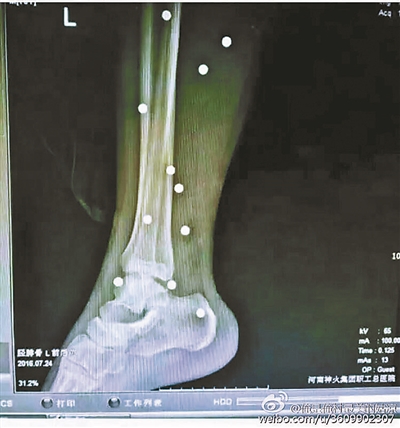

傷者體內(nèi)取出的鋼珠

爆炸導致鋼珠遍布傷者身體各處

黃明的伯伯對北青報記者表示,由于黃明直接踩到了爆炸物,所以傷情最為嚴重,“他的腿被炸斷,身體內(nèi)被炸進了40多顆鋼珠。手術(shù)后已經(jīng)從體內(nèi)取出29顆鋼珠,還有十多顆鋼珠沒有取出來?!备鶕?jù)黃明的入院記錄,他全身有多處爆炸傷,且全身多處異物存留。

爆炸發(fā)生時,陳浩的位置與黃明靠得很近,因此也受傷較重。他告訴北青報記者,經(jīng)過10多個小時的手術(shù)后,醫(yī)生從他身體里取出了12顆鋼珠。目前,他和黃明兩人經(jīng)過手術(shù)后,已從重癥監(jiān)護室轉(zhuǎn)至普通病房。其余三人中,陳剛的臀部受傷,當天晚上在醫(yī)院清理完傷口后便回了家,而同行的兩名女生身上有一些擦傷。